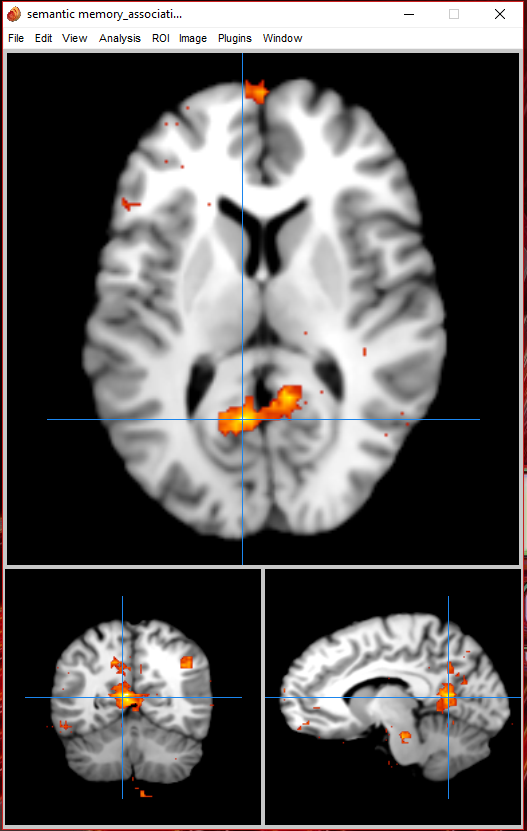

Cognitive process neuroimaging analysis

Brain region chosen for the term

Neurosynth Coordinates Associations:

| Individual voxel | Seed-based network | |||

| Name | z-score | Posterior prob. | Func. conn. (r) | Meta-analytic coact. (r) |

| autobiographical | 10.7 | 0.88 | 0.49 | 0.52 |

| episodic | 9.69 | 0.81 | 0.44 | 0.49 |

| posterior cingulate | 9.52 | 0.78 | 0.54 | 0.53 |

| episodic memory | 8.49 | 0.81 | 0.37 | 0.42 |

| semantic memory | 8.12 | 0.86 | 0.18 | 0.24 |

| retrosplenial | 7.77 | 0.85 | 0.41 | 0.49 |

| retrieval | 7.22 | 0.74 | 0.32 | 0.36 |

| memory | 6.85 | 0.69 | 0.2 | 0.29 |

| memory retrieval | 6.73 | 0.8 | 0.28 | 0.32 |

| concrete | 6.58 | 0.85 | 0.06 | 0.13 |